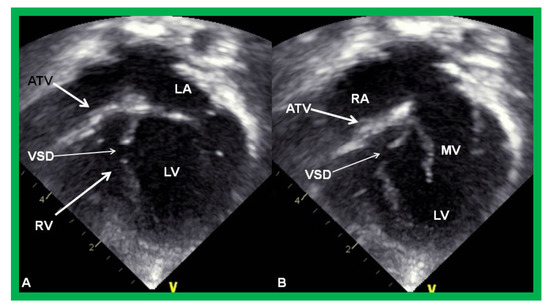

Figure 3.

Echocardiograms in apical four-chamber views of an infant with tricuspid atresia demonstrating a dilated left ventricle (LV), a small right ventricle (RV), and a dense band of echoes at the site where the tricuspid valve echo should be (ATV; thick arrow). Images with closed (A) and open (B) mitral valve are shown; the tricuspid valve remains closed in both situations. A ventricular septal defect (VSD; thin arrow) is also shown. LA, Left atrium; RA, Right atrium.